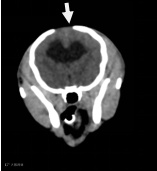

| 大脑右侧顶部脑挫裂伤 |

| 先天性脑囟门未闭合 |

| 右侧顶骨及颞骨骨折 |

3、大脑右侧顶部脑挫裂伤

4、先天性脑囟门未闭合

2、右侧顶骨及颞骨骨折伴周围软组织稍肿胀